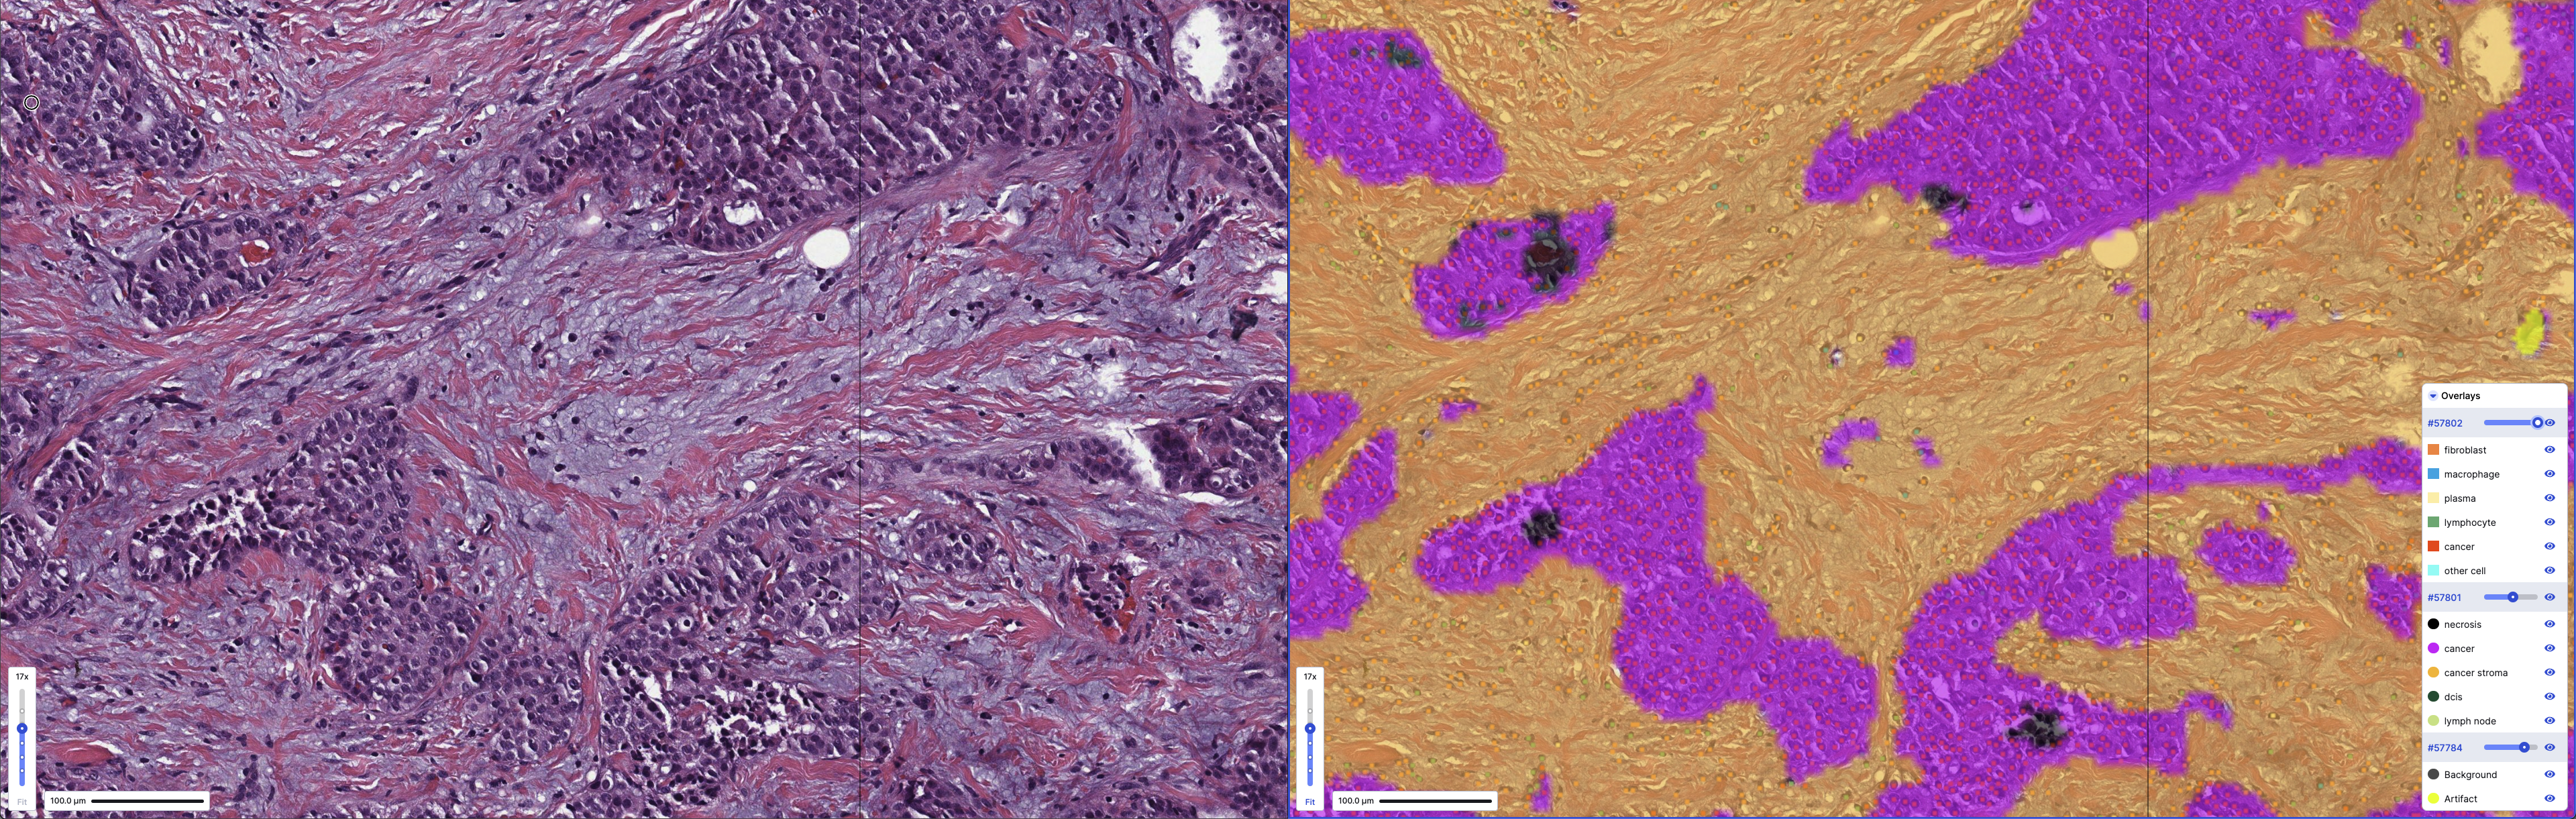

Poster #PO1-15-01: Digital Pathology Models reveal Case-Specific Characteristics of the Tumor Microenvironment

Tumor microenvironments are complex three-dimensional structures, but often only single histological sections are used to glean biological information for research purposes or in some diagnostic practices. These conclusions can also be affected by technical factors in slide preparation and digitization.

In this research, PathAI applied PathExplore, a suite of digital pathology models to identify cell and tissue substances as well as their spatial relationships, to whole-slide images of breast cancer tumors and quantified intra- and inter-tumor heterogeneity in human-interpretable features of the tumor microenvironment.

The results reveal biological and technical variability that can inform selection and interpretation of biomarkers derived from single slides. The ability to uniquely identify slides from the same case additionally demonstrates the technical robustness of digital pathology models for yielding quantitative insights into tumor biology.